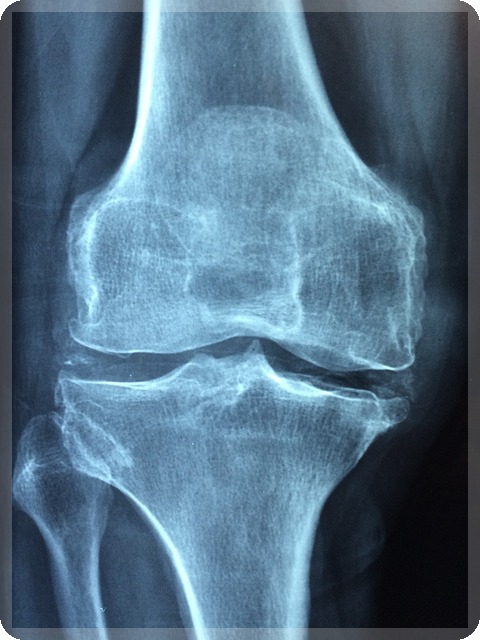

무릎 관절염은 일상생활에 큰 영향을 미치는 퇴행성 질환입니다. 관절 연골의 손상과 주변 조직의 염증으로 인해 다양한 증상이 나타나게 됩니다. 이러한 증상을 정확히 이해하고 적절한 관리를 하는 것이 중요합니다. 이번 섹션에서는 무릎 관절염의 주요 증상에 대해 알아보겠습니다.

관절 내 염증으로 인해 무릎이 붓거나 열감이 느껴질 수 있습니다. 부종은 일시적으로 나타날 수 있지만, 만성적으로 지속될 수도 있습니다. 심한 경우에는 관절액이 차는 활액막염이 발생할 수 있습니다. 시간이 지남에 따라 무릎 모양이 변형되고, O자형 또는 X자형 다리로 변화하는 경우도 있습니다. 이러한 변형은 보행 불안정성 및 추가적인 관절 손상을 초래할 수 있습니다.

무릎 관절염은 다양한 원인으로 인한 염증과 통증이 동伴하는 질환으로, 중증의 경우 수술적 치료가 필요할 수 있습니다. 이번 섹션에서는 관절염 치료의 대표적인 수술적 방법에 대해 알아보겠습니다.